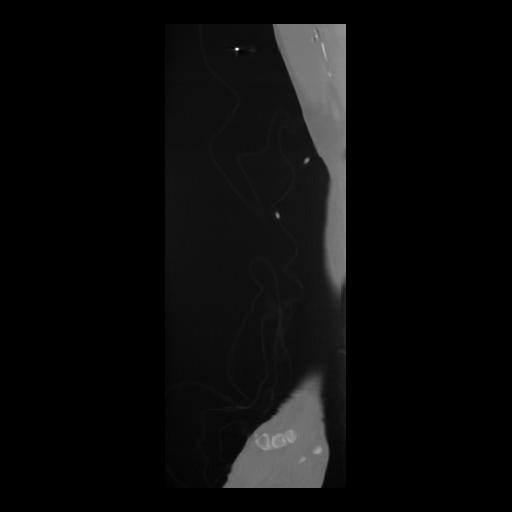

36 CUERPO,CE,Sagittal,3.000,CUERPO,Sagittal,